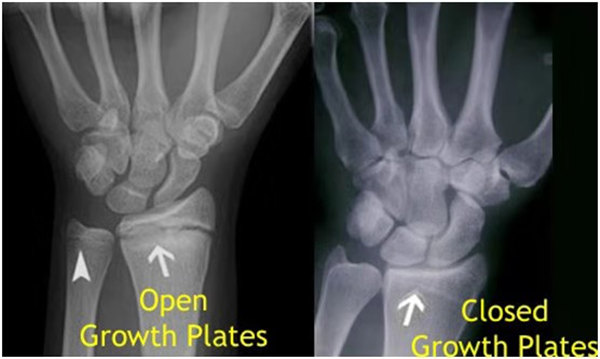

我們都知道,人體的高矮是由骨骼的生長(zhǎng)發(fā)育決定的,特別是下肢長(zhǎng)骨。長(zhǎng)骨呈長(zhǎng)管狀,在長(zhǎng)骨的兩端有一種專(zhuān)管骨骼生長(zhǎng)的骺軟骨,它與干骺端之間有一盤(pán)狀軟骨結(jié)構(gòu)稱為骺板(線),在幼兒的X光片上表現(xiàn)為一條較寬的透光帶。 (見(jiàn)下圖)

未成年時(shí)隨著年齡的增加骺軟骨端不斷骨化,骨骼就不斷增長(zhǎng)。當(dāng)骨骺線完全閉合時(shí)骨骼就停止生長(zhǎng),個(gè)子也就不再增長(zhǎng)了。一般骨骺端完全閉合的年齡是18~20歲左右。